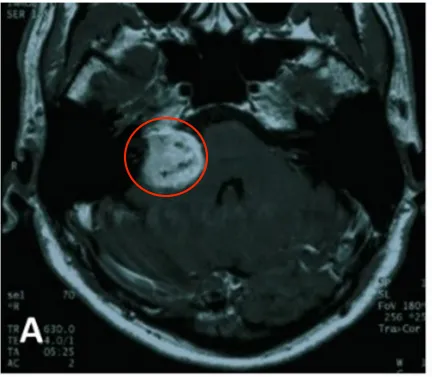

A.2004年4月最初等MR图像,显示右侧桥小脑角(CPA)区肿瘤不均匀强化。